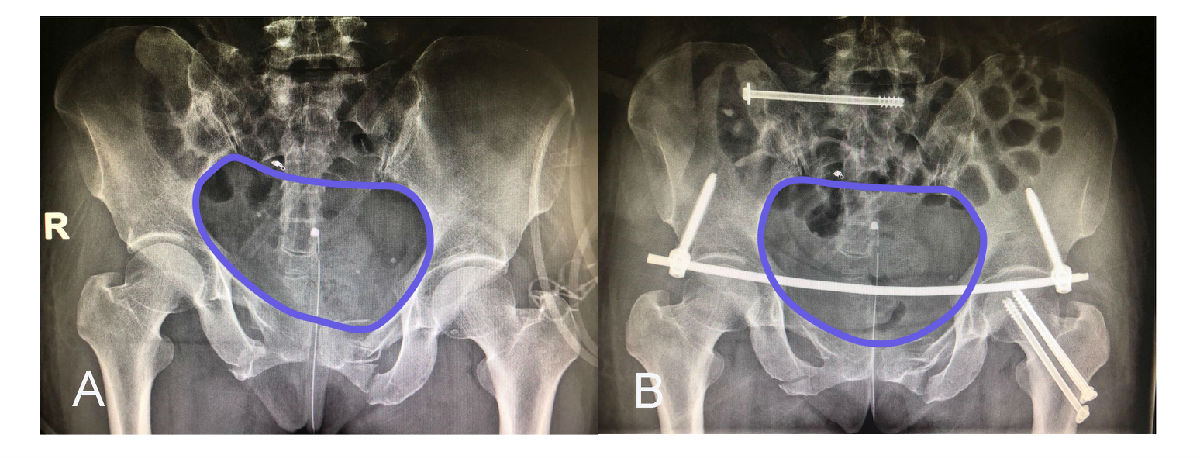

A 术前骨盆平片提示骨盆骨折后骨盆环移位变形;B 经微创治疗后,骨盆骨折获得良好的复位,骨盆环恢复解剖形态。